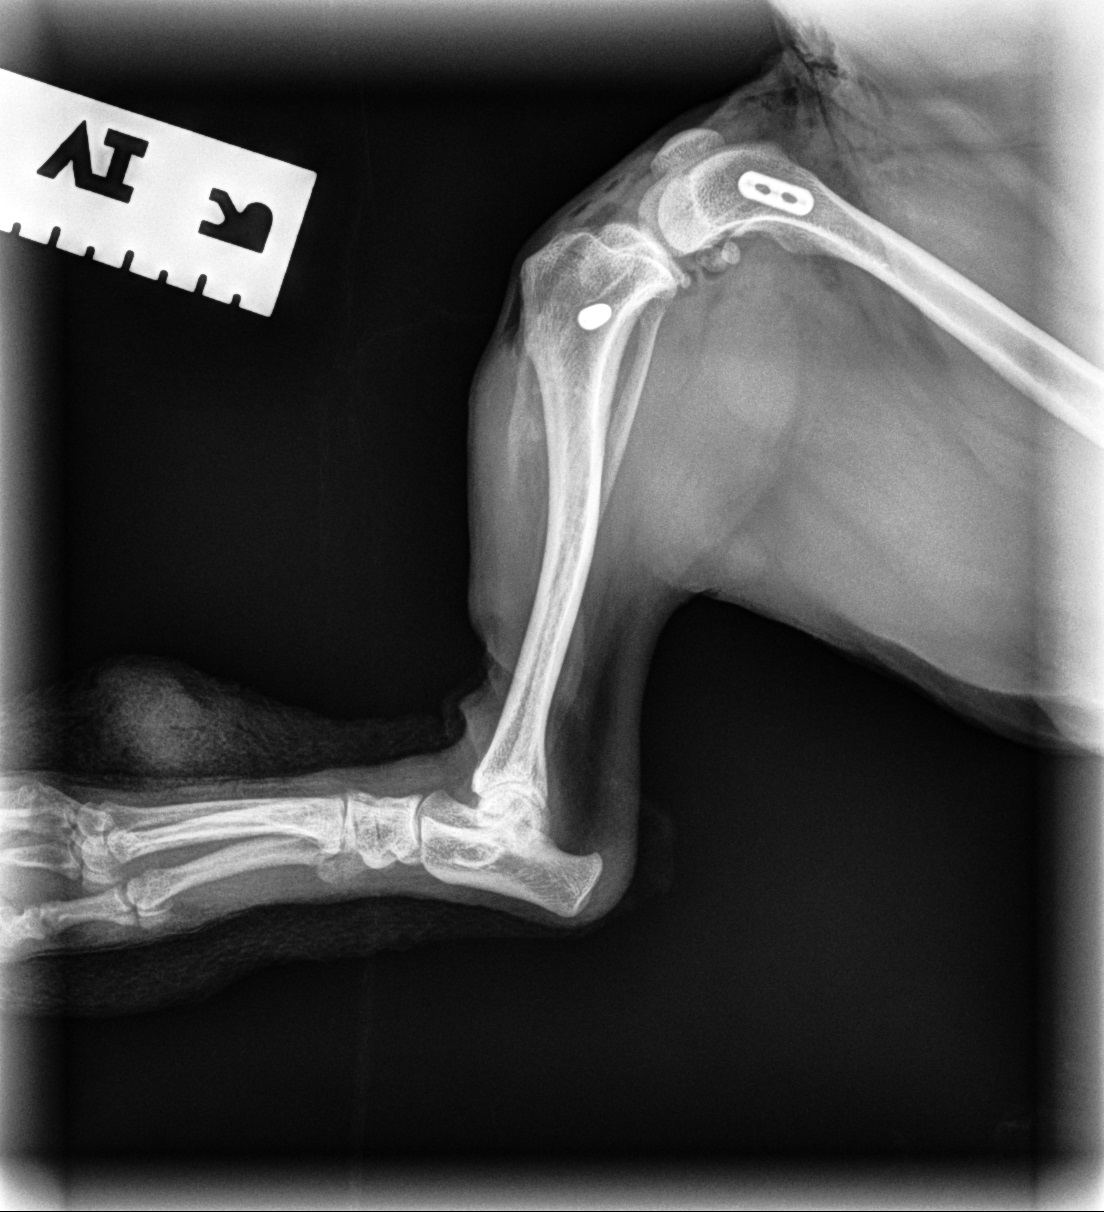

Femoral Head Ostectomy (FHO) Surgery

FHO surgery is an option for pets with severe hip pain due to conditions such as hip dysplasia, trauma, or chronic arthritis. By removing the damaged portion of the hip joint, pain can be significantly reduced, allowing many pets to regain comfortable mobility with proper rehabilitation.

Hip Dysplasia with Arthritis

Femoral Head Ostectomy (FHO) Before Surgery